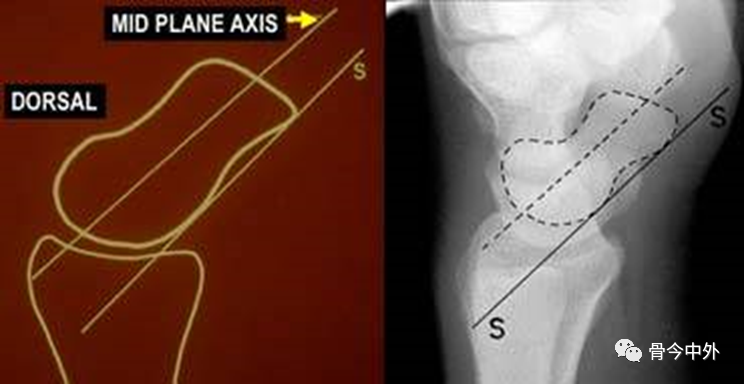

图25 舟骨轴线

中轴线:近极和远极中点连线,常难以分辨;腹侧切线:与中轴线几乎平行。

图26

月骨轴线

通过近侧凸面和远侧凹面中点的连线,与通过月骨掌侧和背侧边缘的连线垂直(左图)。

舟月角(右图)

正常:30– 60°

可疑异常:60– 80°异常:> 80°,提示腕关节不稳